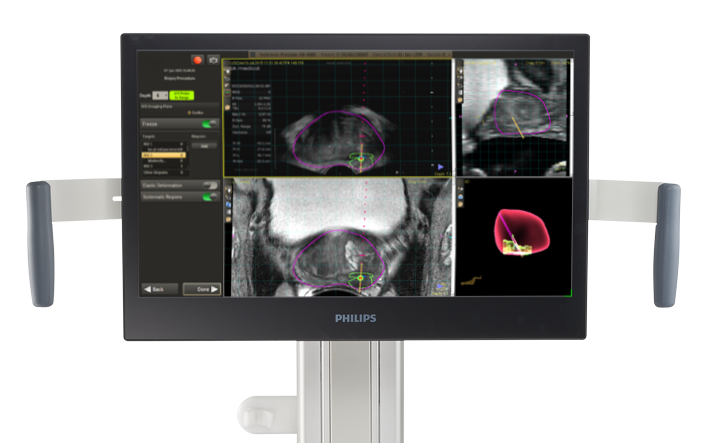

Monitor

El monitor tiene un diseño ergonómico totalmente articulado. Sus múltiples posibilidades de ajuste permiten un mayor rango de ángulos de visualización durante los procedimientos. Además, se pueden realizar ajustes de altura para obtener una mayor flexibilidad.